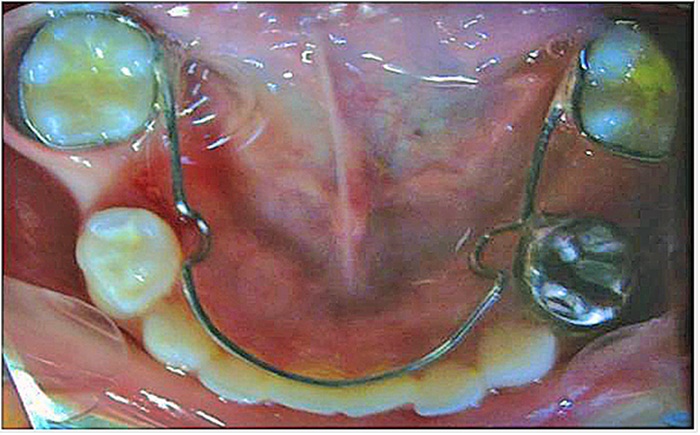

Esta última se adaptó ubicando el tubo hacia distal, a fin de utilizar esta porción como retenedor para el fantoche del segundo molar inferior izquierdo. Se tomó la impresión de arrastre para obtener los modelos de trabajo sobre los que se elaboraron los dos mantenedores de espacio tipo zapato distal propioceptivo. Luego de un correcto pulido, se cementaron con ionómero de vidrio 3M® (Ketac® Cem Easymix). Se indicó al paciente seguir una dieta blanda las primeras 2 horas después de la cementación, para evitar desadaptaciones del dispositivo, y una estricta higiene bucal. Los controles se efectuaron cada tres meses y, cuando erupcionaron los primeros molares permanentes, aproximadamente a los nueve meses, se utilizaron estos como pilares para confeccionar el arco lingual (figura 6).